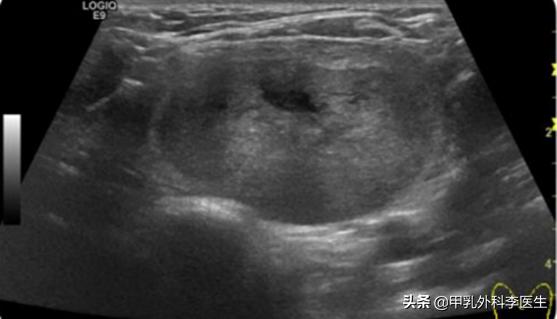

术前肿块体积:4.8cm*3cm